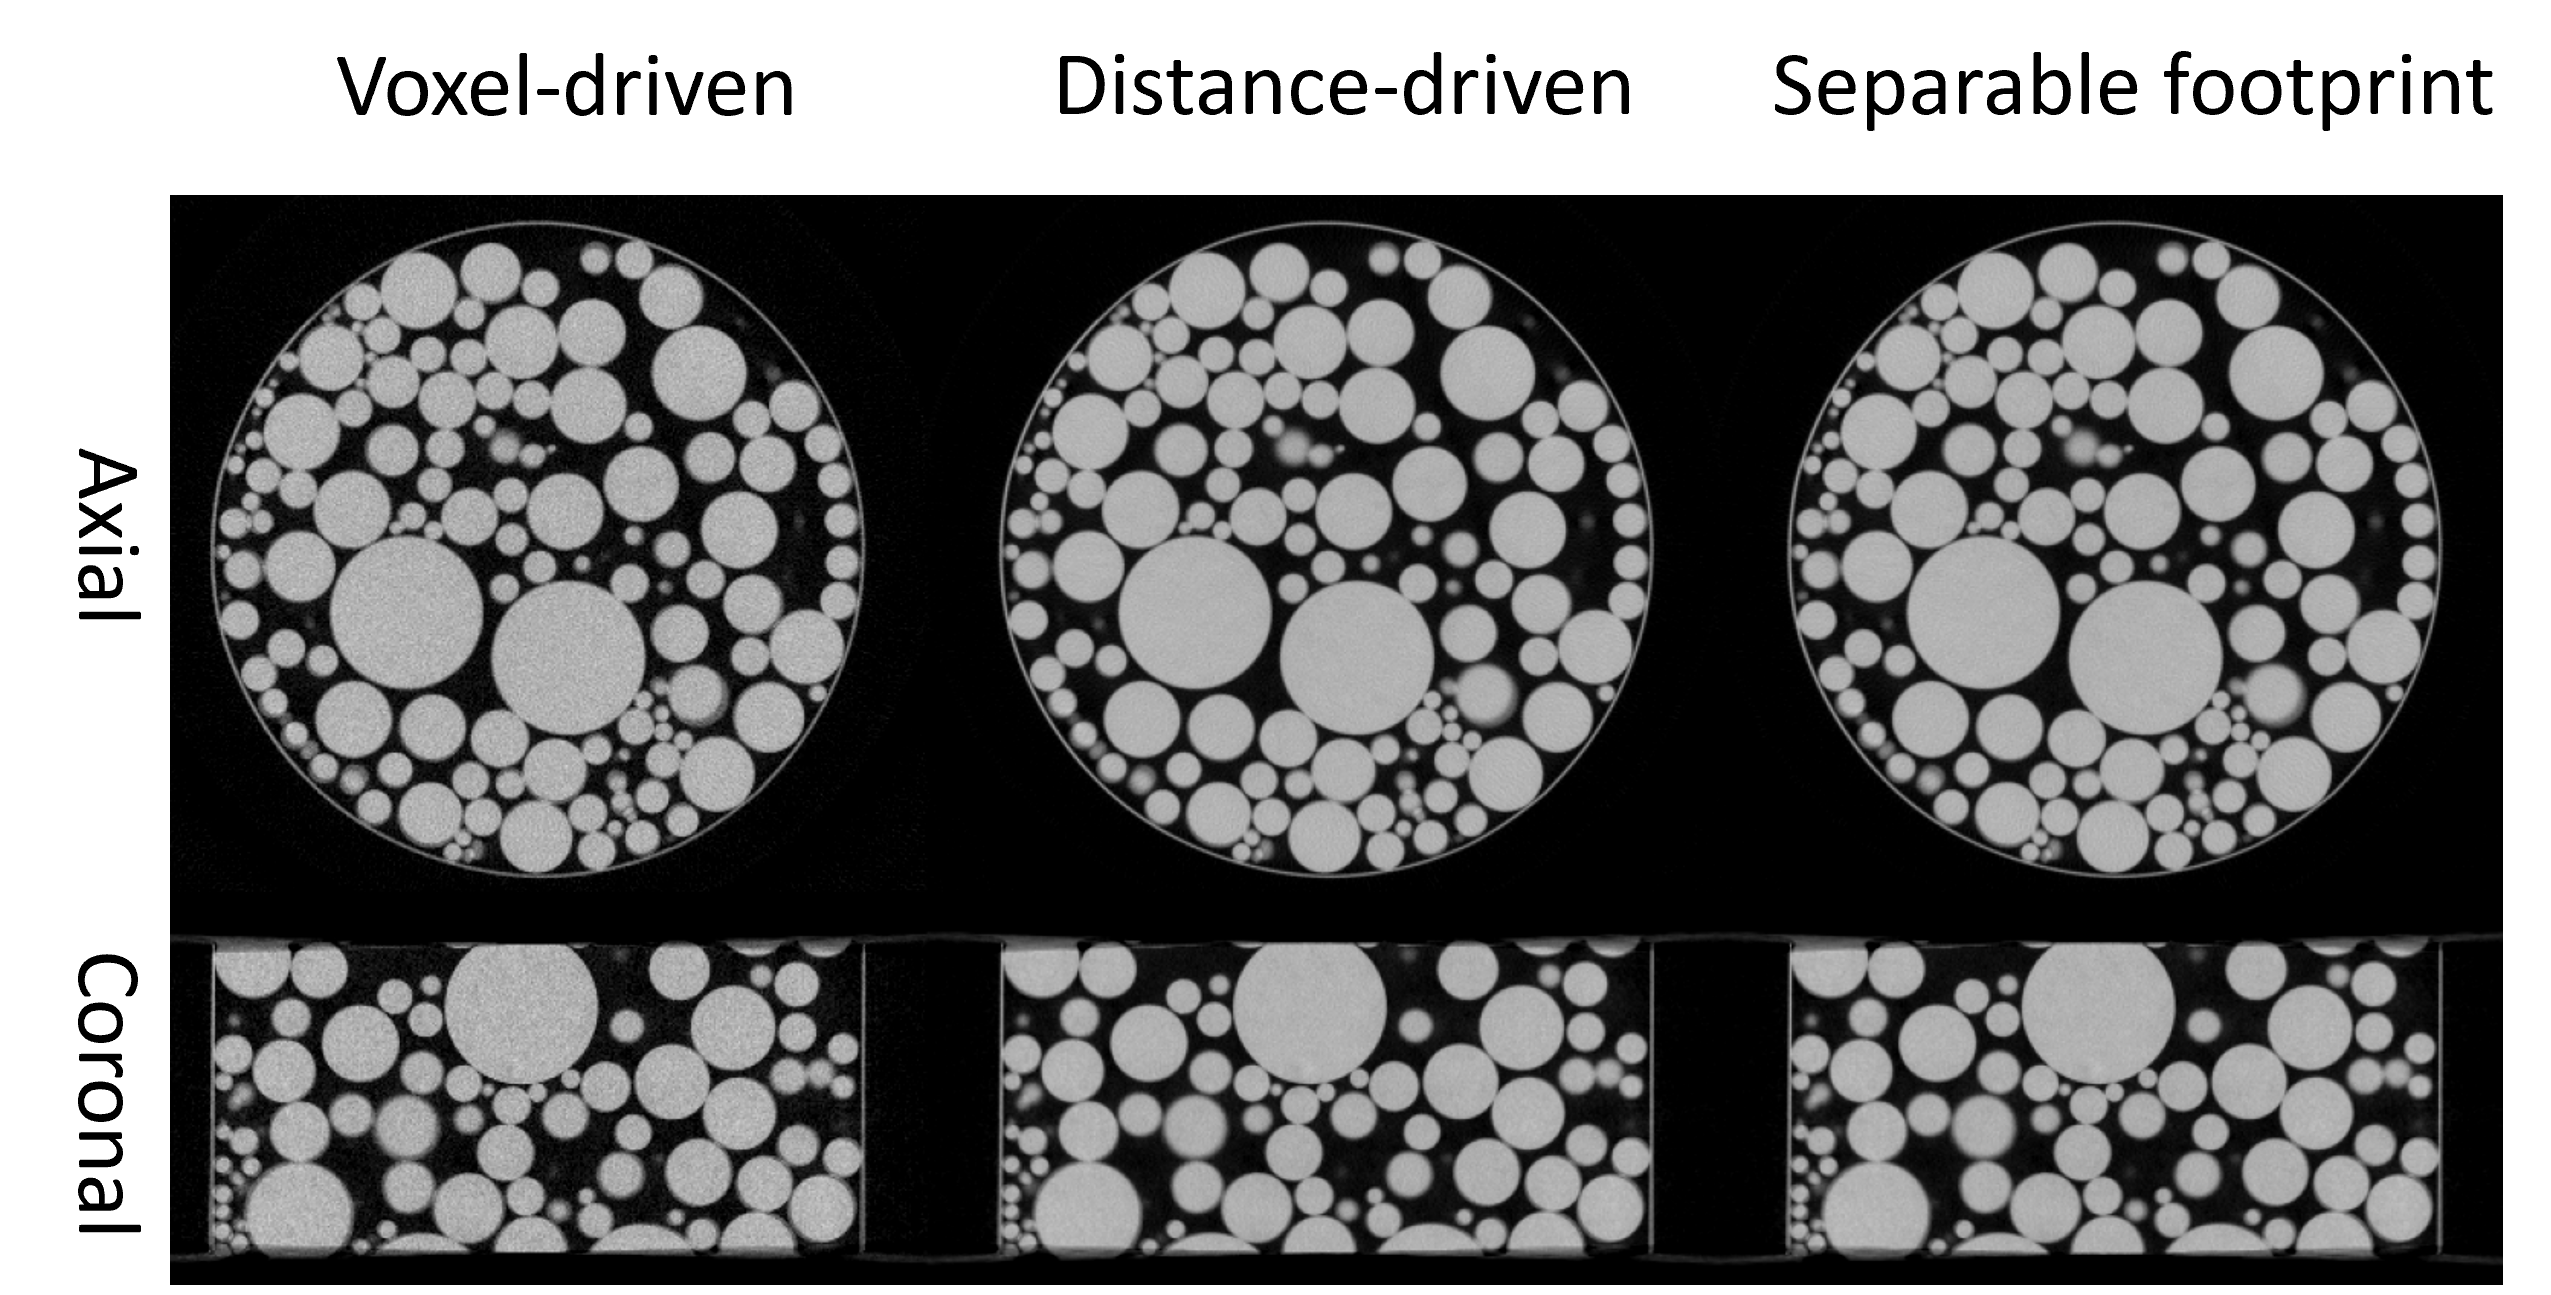

Refer to caption

Figure 4: FBP reconstruction using the top-layer projections from a dual-layer CBCT system wiht different projector algorithms.

We validated the CTorch projector for both circular and non-circular geometries using physical x-ray bench data. A plastic ball phantom was scanned on a laboratory benchtop CBCT system equipped with a dual-layer flat-panel detector[22]. The two-layer projections were reconstructed separately using the FBP algorithm under a 3D circular geometry assumption. Fig. 5 presents the reconstruction results for the top layer using different projectors. Each projector accurately depicts the ball shape with sharp edges, demonstrating the high geometric accuracy of the CTorch circular-scan projector. Fig. 5 shows the bottom-layer results. When the projections are backprojected under the circular geometry assumption, geometric distortions are noticeable, particularly around the ball edges. These distortions may arise from misalignment of the detector pixel grids between the two layers. However, by shifting to a non-circular geometry model that incorporates a 0.4°0.4°0.4\degree0.4 ° in-plane detector rotation, the distortions are substantially reduced. This validates the accuracy of the CTorch non-circular projector and highlights the importance of flexible geometry descriptions for processing nonideal physical projection data.